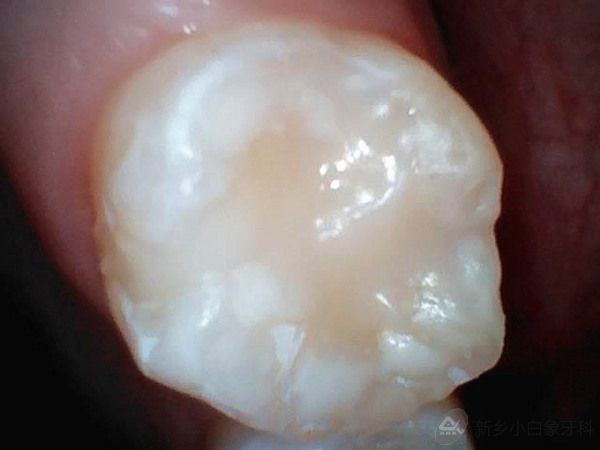

患者廉某某,女,10岁,患儿家长发现患儿牙齿有洞,影响进食,于2014年12月11日来诊。

检查:16合面及颊沟龋坏达牙本质浅层,探诊(-),叩诊(-),温度测试正常,牙龈无红肿。

诊断:16中龋

治疗计划:16护充

治疗过程:3%双氧水含漱一分钟,16去腐质,备洞,隔湿干燥,流动纳米充填及行纳米封闭术。